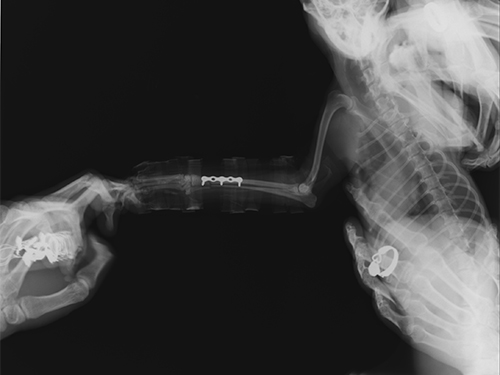

主诉:该犬从椅子上跳落后右前肢不能着地,稍有碰触即疼痛惨叫。CR显示该犬右前肢桡尺骨骨折,经协商后实施骨折内固定手术。三周后着地,走路无异常。一个月后痊愈。

图3:术后正位片